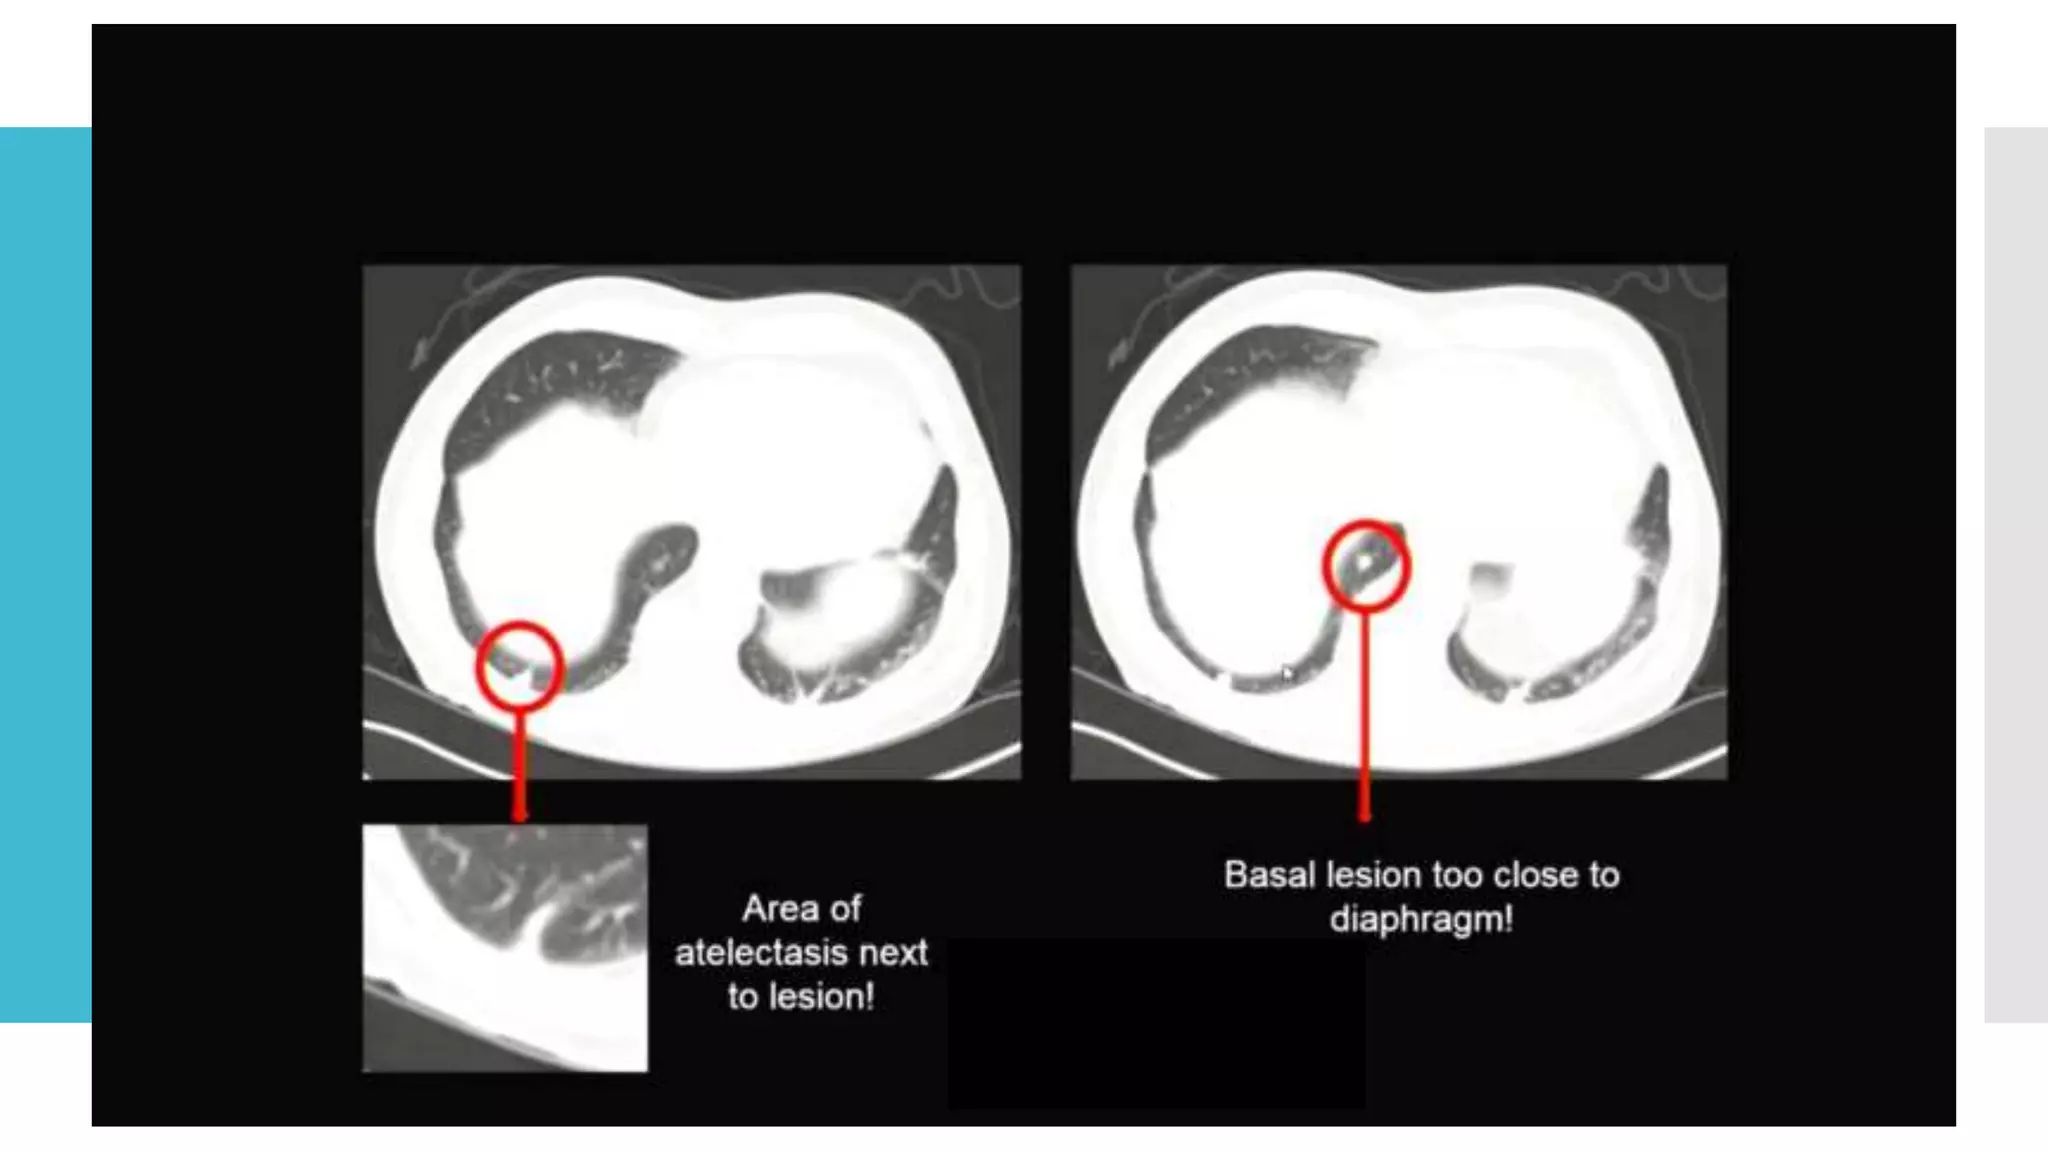

Reproducible

repeated

measurements

 Do not necessarily select the largest lesions as targets.

 Lesions should be those that lend themselves to

reproducible repeated measurements